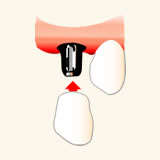

あごの骨に人工的な歯根を埋め込みます

手術によって顎の骨に「人工的な歯根(インプラント)」を埋め込みます。

人工的な歯根に人工的な歯をかぶせます

その上に「人工的な歯(歯冠)」をかぶせることで再び噛めるようになります。